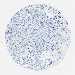

CANCER BREAST CANCER Show tissue menu

BRCA TCGA BRCA VALIDATION PROTEIN EXPRESSION

ANTIBODIES

AND

VALIDATION